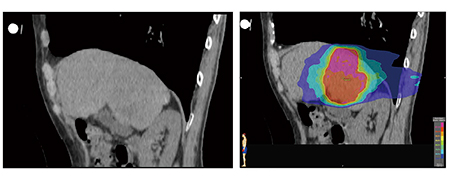

当クリニックにおけるIMRTの約9%は転移性脊椎腫瘍の再発症例である。初期治療を上回る高線量の照射を行うために,われわれは前回の治療と今回の治療における線量分布図を重ね合わせて累積線量を評価し,治療可能かどうかを判断している(図1)。しかし,実際の治療中には,患者の動きによりターゲットのズレが生じてしまう。そこでわれわれは,CTから得たDICOM-RTのデータから線量分布を解析できるソフトウエア“ShioRIS 2.0”を用いて体動のシミュレーション解析を行い,安全で確実な照射を実施している。

図1 転移性脊椎腫瘍再発例に対する治療戦略